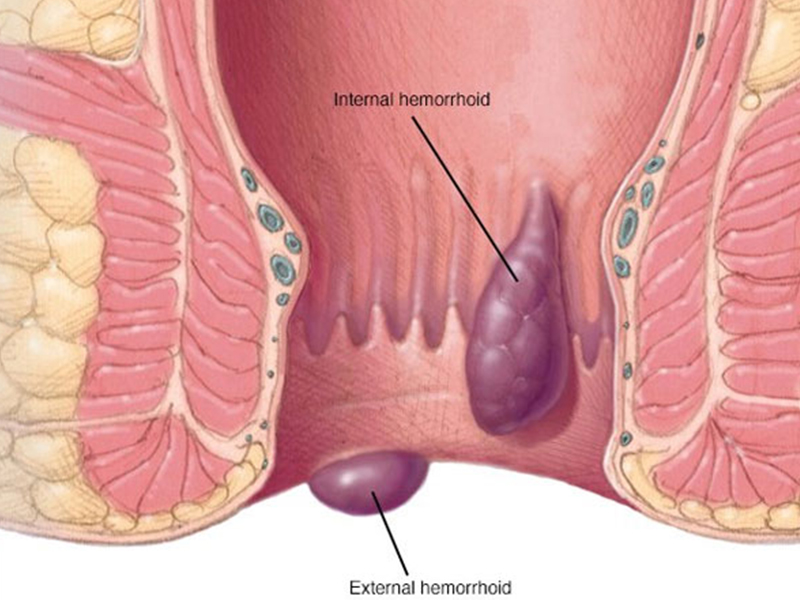

Piles

Hemorrhoids (piles) are blood vessels located in the smooth muscles of the walls of the rectum and anus. They are a normal part of the anatomy and are....